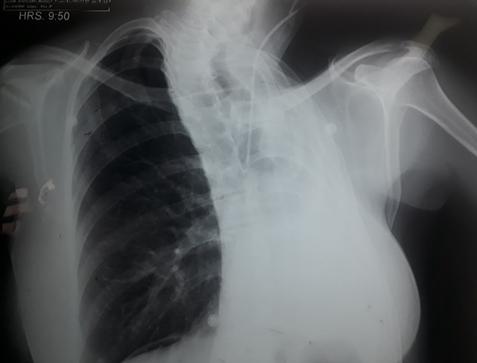

Create a flipbook

Issuu converts static files into: digital portfolios, online yearbooks, online catalogs, digital photo albums and more. Sign up and create your flipbook.